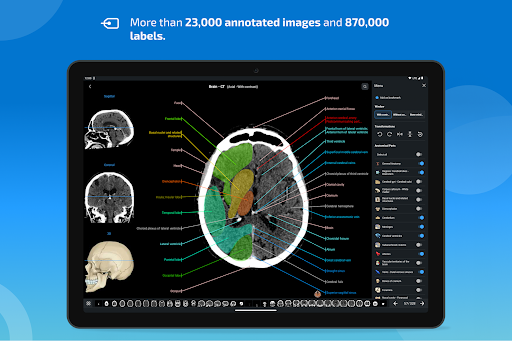

-The pins mode have a new behaviour allowing you to follow an anatomical structure much more easily

-You can now manually select the font size you prefer for your anatomical structures labels (in labels mode)

-Within the details view of an anatomical structure, a pin now points the related structure in all present images

Also tap directly on the image to navigate to the presented image in that module